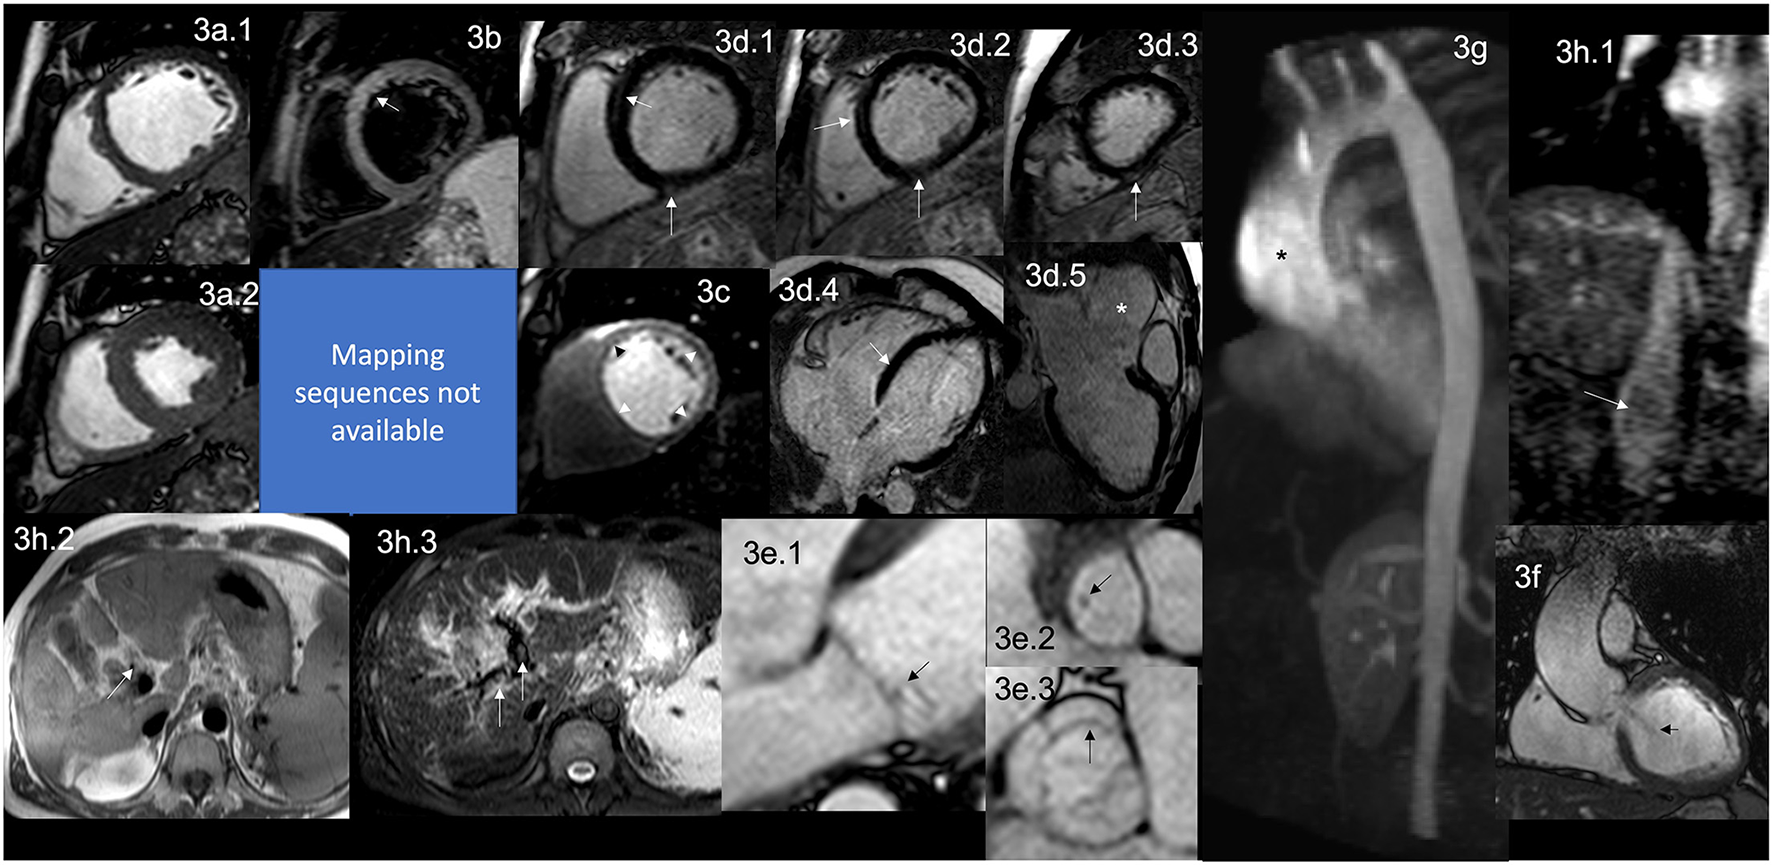

Figure 3

CMR findings in APS. A figure demonstrates the array of findings from a comprehensive CMR study at a 1.5 Tesla scanner of APS. (a) SSFP sequence still cine images in short-axis view at the mid-ventricular level in end-diastole (a.1) and end-systole (a.2) show normal global and regional right and left ventricular functions, LVEF 63% and RVEF 56%. (b) T2-W STIR sequence in short-axis view at a mid-ventricular level shows mildly increased signal intensity in the anterior and anteroseptal segments (arrow) with a myocardial/skeletal muscle ratio of 3.6 suggestive of myocardial edema. (c) Stress CMR with FPP T1-W sequence with adenosine infusion at 140 mcg/kg/min over 6 mins showing a subendocardial circumferential perfusion defect (arrowheads) consistent with subendocardial ischemia due to endothelial dysfunction and probably to a microvascular disease (no obstructive coronary artery disease demonstrated in ICA). (d) LGE PSIR sequence. (d.1–3) short-axis views at basal (d.1), mid (d.2), and apical (d.3) levels, and long-axis views in 4-chambers (d.4) and 3-chambers (d.5) projections. The arrows in these images demonstrate areas of focal fibrosis as mid-wall LGE in the anteroseptal segment in (d.1,d.2,d.4); and in the subepicardium of the inferior segment from the base to the apex. (d.5) Shows aortic root and ascending aorta dilatation confirmed by the CE-MRA in (g) and the coronal view in SSFP still cine image (f), where it also demonstrates the presence of aortic regurgitation (arrow). (e) Zoomed still cine images in SSFP sequence of the mitral valve (e.1) and a fused asymmetric bicuspid aortic valve (e.3) Showing in a 4-chambers view a small isointense nodule in the ventricular side of the mitral valve, suggestive of Libman-Sacks endocarditis (arrow) and in the LVOT [arrow in (e.2)] (confirmed by echo), and mild thickening of the fused coronary bicuspid cusp [arrow in (e.3)]. Additionally, images (h.1–3) Show a thrombus within the portal vein and its main branches; in (h.1), a venous phase of the CE-MRA shows a contrast defect within the portal vein (arrow) consistent with a thrombus. T1-W axial view of the liver (h.2) shows a hyperintense structure within the portal system (arrow), and a T2-W STIR view of the liver (h.3) shows hypointense masses within the main portal branches (arrow) consistent with thrombus. CMR, cardiovascular magnetic resonance; SSFP, steady-state free precession; LVEF%, left ventricular ejection fraction; RVEF%, right ventricular ejection fraction; T2-W STIR, T2-weighted short-tau inversion recovery; FPP, first-pass perfusion; T1-W, T1-weighted; ICA, invasive coronary angiography; LGE, late gadolinium enhancement; PSIR, phase-sensitive inversion recovery; CE-MRA, contrast enhancement magnetic resonance angiography; LVOT, left ventricular outflow tract.

It is well described that APS affects the heart valves in approximately 30% of the patients (68). Recently, the association of Libman-Sacks endocarditis with primary APS, and not only when associated with SLE, have been made and demonstrated that it is due to thrombosis and thickening of the valves with the formation of sterile fibro-fibrinous vegetations of the mitral and/or aortic valves on their endocardial surfaces (68–71) (Figure 3e.1–3).

The typical functional abnormality is non-hemodynamically significant mitral and aortic regurgitation, the most frequently affected mitral valve. This valvular involvement is reported as persistent or even progressive over time regardless of the anticoagulant or antiplatelet therapy. Clinically, most patients remain asymptomatic for a long time, but eventually, they will require surgical treatment (68).

Intracardiac thrombosis is rarely reported (72); it produces masses in all four cavities (73–76), and even recurrent masses (77); usually adherent to the endocardial surface (74). These thrombotic masses mimic myxomas (73) or other tumors, even primary ones, by Echo (72). In addition to the presence of cardiac masses, the complication of frequent peripheral embolisms, particularly in the brain, is reported (72).

LV dysfunction is a rare presentation (84, 85) and the suspected mechanism identified in the autopsy is a widespread thrombosis of the intramyocardial arteries and arterioles (86, 87), which one can assume leads initially to microvascular dysfunction, then microinfarctions of the myocardium generating small scars and fibrosis and finally compromising the ventricular function. Myocardial edema (Figure 3b) has (88) also been described as catastrophic (89).

Ischemic heart disease is generally caused by microvascular endothelial dysfunction (Figure 3c) with or without associated micro thrombosis (86) and minimal inflammation (92).

Myocardial infarction (MI) is due to thrombosis or vasospasm (68) of the large epicardial coronary arteries. MI could be the first manifestation of the disease (93, 94).

CMR has identified a high prevalence of myocardial scar (95), diffuse fibrosis (88) (Figure 3d.1–4), and endomyocardial fibrosis (96–98).

As mentioned before, APS can have many cardiovascular manifestations. Therefore, the “APS Task Force” has taken valvular heart disease related to APS as one of the “extra criteria” for its diagnosis (99). Even though echocardiography is usually the first non-invasive imaging technique for evaluating APS-related VHD, CMR has certain advantages, such as tissue characterization, LGE for detecting myocardial fibrosis, and adequate VHD evaluation.

Sacré et al. evaluated 27 consecutive patients with established diagnosis of APS matched with 81 patients without known cardiovascular disease and who developed CMR. LGE was present in 29.6% of APS patients, with a typical ischemic pattern in 11.1%. Remarkably, myocardial scarring had no electrocardiographic nor Echo evidence. Authors concluded that CMR helps search for myocardial ischemia and myocardial fibrosis in APS patients even if they are asymptomatic (95) as CMR can detect scar in as little as 1 cm3 of tissue.

Since VHD is the most frequent CV manifestation in APS but also myocardial fibrosis, silent ischemia, potential HF, and the presence of thrombus in different sizes might be present (68), CMR might be the non-invasive cardiovascular image of choice in these populations for correct and prompt evaluation of all of these manifestations in APS patients.

Echo helps detect many of the CV involvement in APS. It has many advantages, such as broad availability and the possibility of performing the study on the patient's bed and in hemodynamically unstable ones. As a single modality, it is cheaper. However, it cannot detect the earliest involvement related to tissue characterization such as minor myocardial edema, inflammation, or diffuse fibrosis before it can modify global function or even more sensitive techniques such as strain. CMR can identify in a single study the involvement of different components of the CV system, including great vessels, lungs (where are grossly affected by its vasculature), and stress perfusion with high reproducibility allowing the patient to be its control in the future. It would be necessary to gather information from different imaging modalities such as echo, CT, nuclear, etc., impacting more tests, radiation exposure, and costs (101).